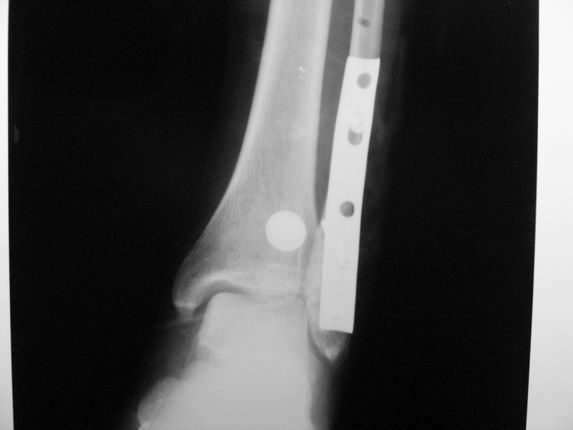

Уважаемые коллеги! Как и обещал, представляю плоды своей работы. Хвалиться особо нечем. Пошли задним

доступом сначала к м/берцовой кости, благодаря смещению линию перелома удалось сразу дифференцировать и по ней узким долотом (без молотка) мобилизовали отломки. Затем выделили задний край, там было проще пройти по линии перелома. Далее пластина по задней поверхности в дистальный отломок, винт проксимальнее пластины и дистрактором с трудом растянули отломки, ощущение было идеальной репозиции м/берцовой кости( доступен осмотр по задней и наружной поверхности), далее винты стандартно. Кстати, положение больной на боку: очень неудобно, но по-другому потом не повернуть на спину, чтобы сделать снимки в стандартных проекциях (ЭОПа нет). Затем дистрактор (два полукольца, спицы), репозиция заднего края, спонгиозный винт с шайбой, слишком проксимально, поэтому + еще один. Доступ к дельтовидной связке: рубец в передней порции, частично иссечен, шов. В общем, длительность операции 3,5 часа, а сказать, что все задуманное получилось, не могу.

А.Минервин.

Отправитель: Djpldas Kuldjanov 16 Март 2006, 17:11

Отличная, грамотная работа, поздравляю, я бы держал в гипсовой повязке до трех недель, затем разработку сустава без нагрузки, нагрузку при такой фиксации,

думаю, можно начать в 6 недель.

Все таки нужно было стянуть ДМС. Судя по снимкам остался подвывих.

Отправитель: Alexander Chelnokov 16 Март 2006, 17:18

Да все прилично получилось, и случай ведь запоздалый, так что все труднее было, чем обычно. Так что присоединяюсь к поздравлениям!